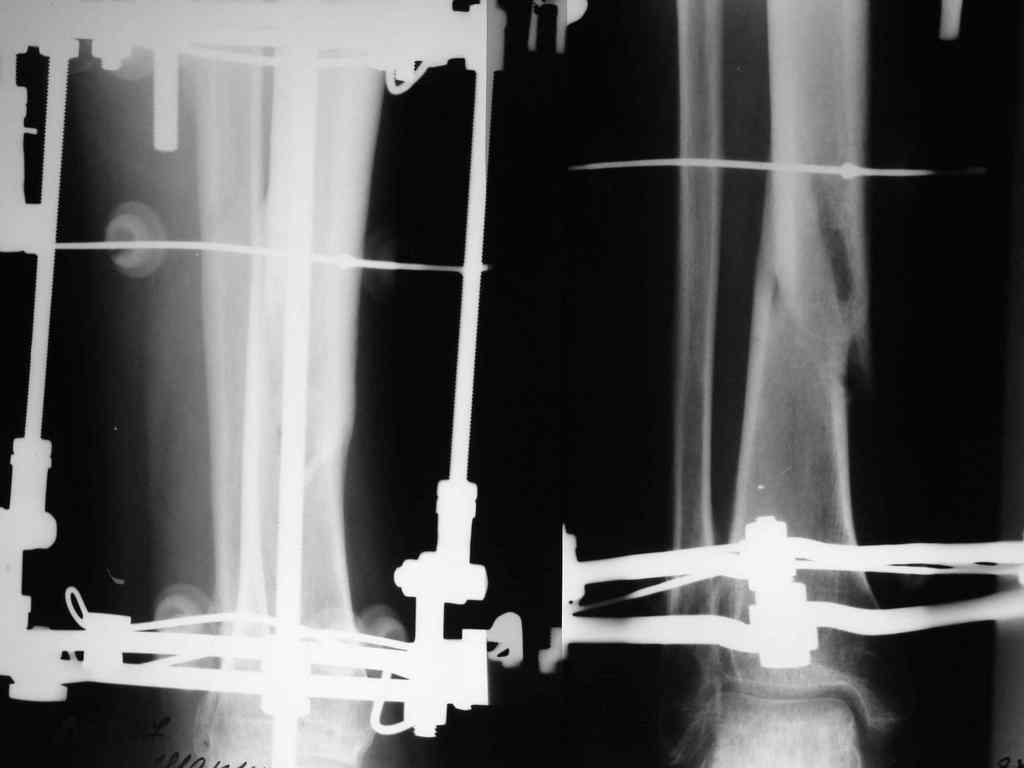

И ещё: Имеется у нас пациент с переломом обеих костей левой голени. Перелому 13 месяцев. После 6-ти месяцев фиксации в гипсе был наложен аппарат Илизарова.

После коррекции длинны и оси конечности аппарат стабилизирован. В аппарате 7 месяцев. Последние снимки прилагаются. Консультирован на консультативном приёме в УНИИТО. Рекомендовано ослабить аппарат на 20 мм.(!) и ходить с полной нагрузкой на конечность. Убедительная просьба рассмотреть вариант лечения данного пациента в условиях УНИИТО (МОС блокируемым стержнем), т.к. пока не располагаем набором развёрток.

Если судить по рентгенограммам, то перелом сроссЯ, причем месяца два назад. Проведите клиническую пробу, и не надо ничего усложнять.

Согласен с оценкой Александра Артемьева. Не могли бы Вы пояснить, какие соображения при таких рентгенограммах мотивируют к реостеосинтезу?

Перелом сросся.

Снимайте аппарат.